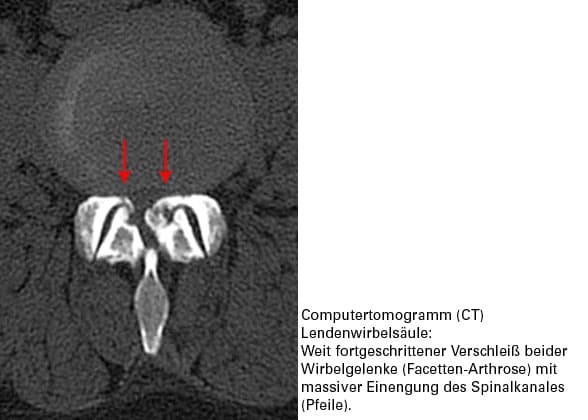

Wenn die Distanzscheibe zwischen 2 Wirbeln, also die Bandscheibe, dünner wird, treten die Wirbel näher aufeinander zu. Die Wirbelgelenke geraten unter einen erhöhten Druck. Gleichzeitig wird die betroffene Bandscheiben-Etage instabil. Das Scharnier Wirbelgelenk bekommt ein krankhaftes Bewegungsspiel, das Gelenk selbst wird instabil.

Instabilität des Wirbelgelenkes unter erhöhter Druckbelastung – diese Kombination löst Verschleißerscheinungen im Gelenk selbst aus. Wir sprechen von einer Wirbelgelenksarthrose (Facetten-Arthrose). Wenn die Bewegungen im Wirbelgelenk von der Muskulatur nicht präzise und stabil geführt werden, kommt es zu Fehlbelastungen im Gelenk. Dies verursacht Schmerzen. Diese werden meist stichartig empfunden. Die Wirbelsäule versucht sofort, den Schmerz "abzuschalten".